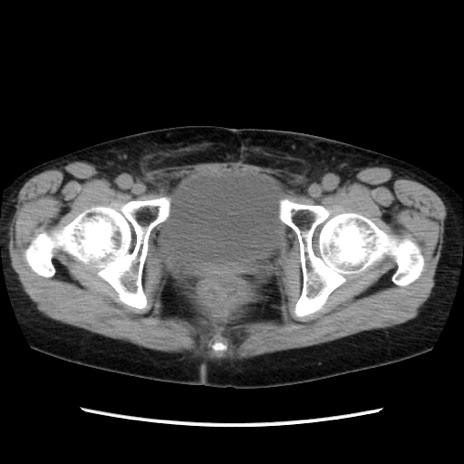

症例32(横断像)

【症例】40歳代 女性

【主訴】上腹部痛、嘔気・嘔吐

【現病歴】約9時間前頃から急に上腹部痛、嘔気、嘔吐が出現。改善しないため救急要請。

【既往歴】子宮頚癌(広汎子宮全摘術、放射線療法)、腸閉塞

【身体所見】腹部:平坦、軟、腸雑音亢進、上腹部を中心に腹部全体に圧痛あり。

【データ】WBC 8400、CRP 0.03